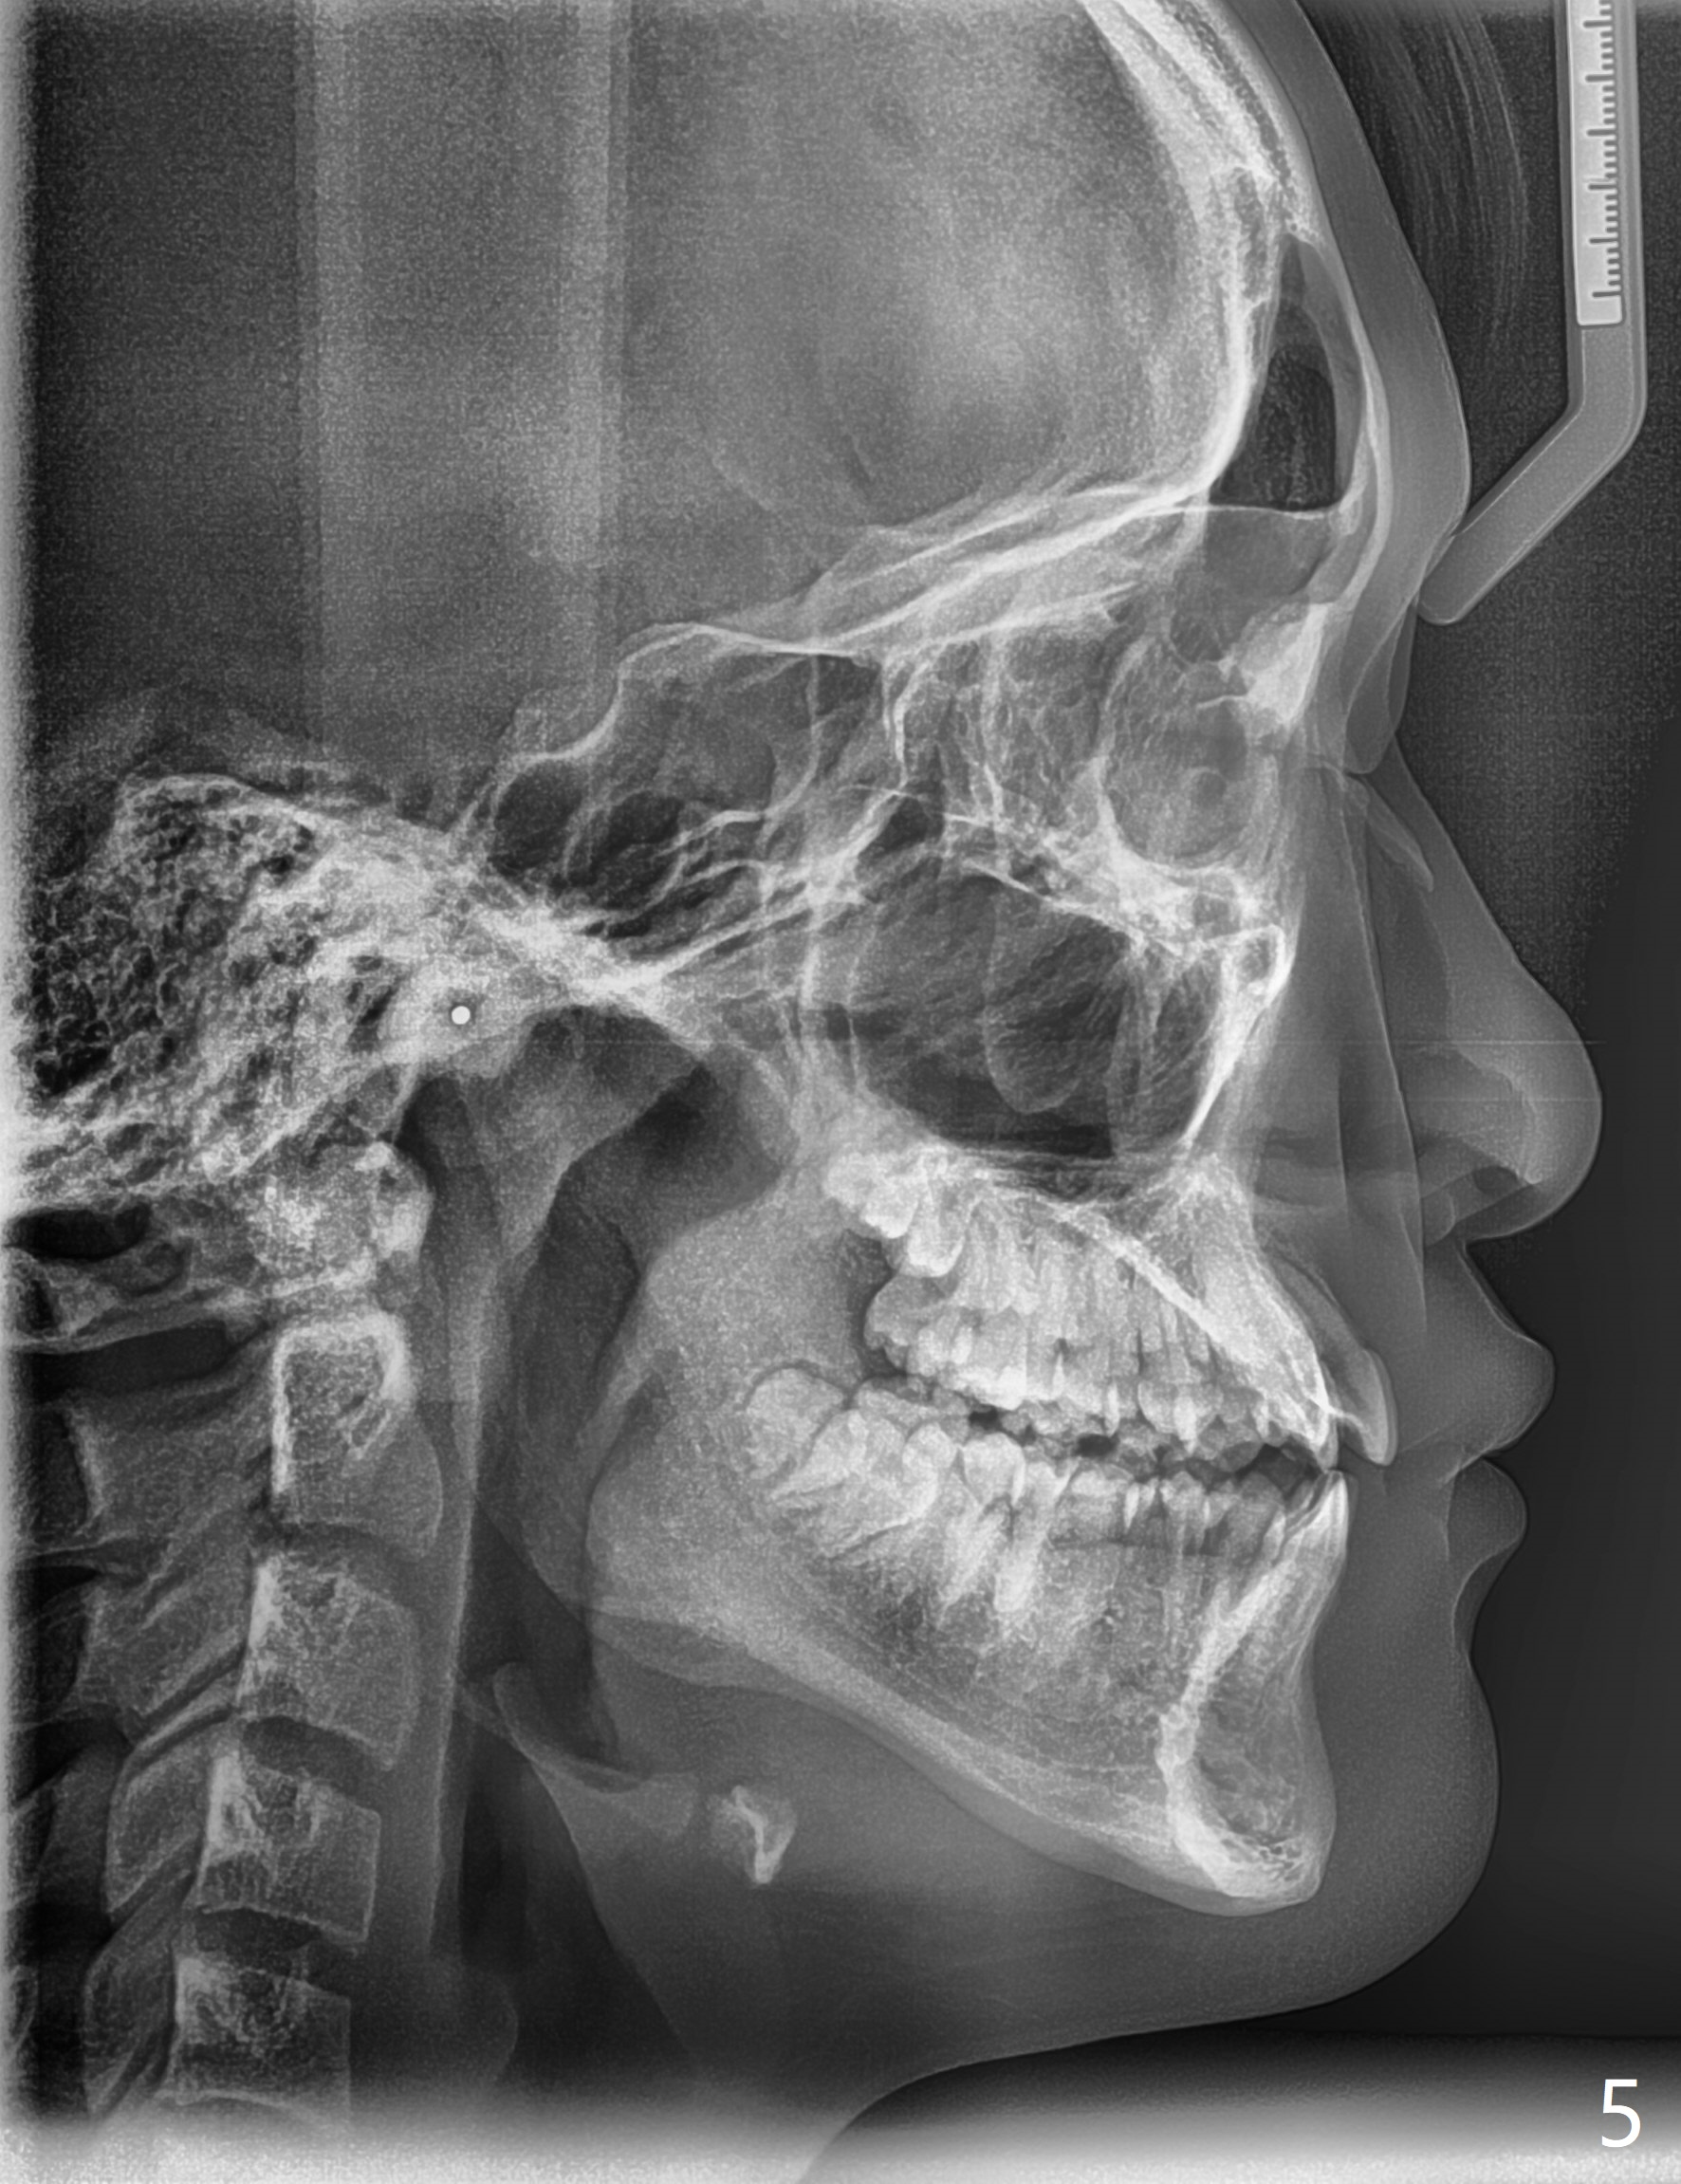

The upper dental midline of a 14-year-old man deviates the left (Fig.1,2,8) with midfacial concavity (Fig.3,4). The upper lateral incisors have cross bite, more severe on the left (Fig.6-8). Can we use open coil spring on the left first, a few months before the right, more or less to help correct the upper midline deviation? Cephalometric analysis shows Class III skeletal relationship (Fig.5,5',11).